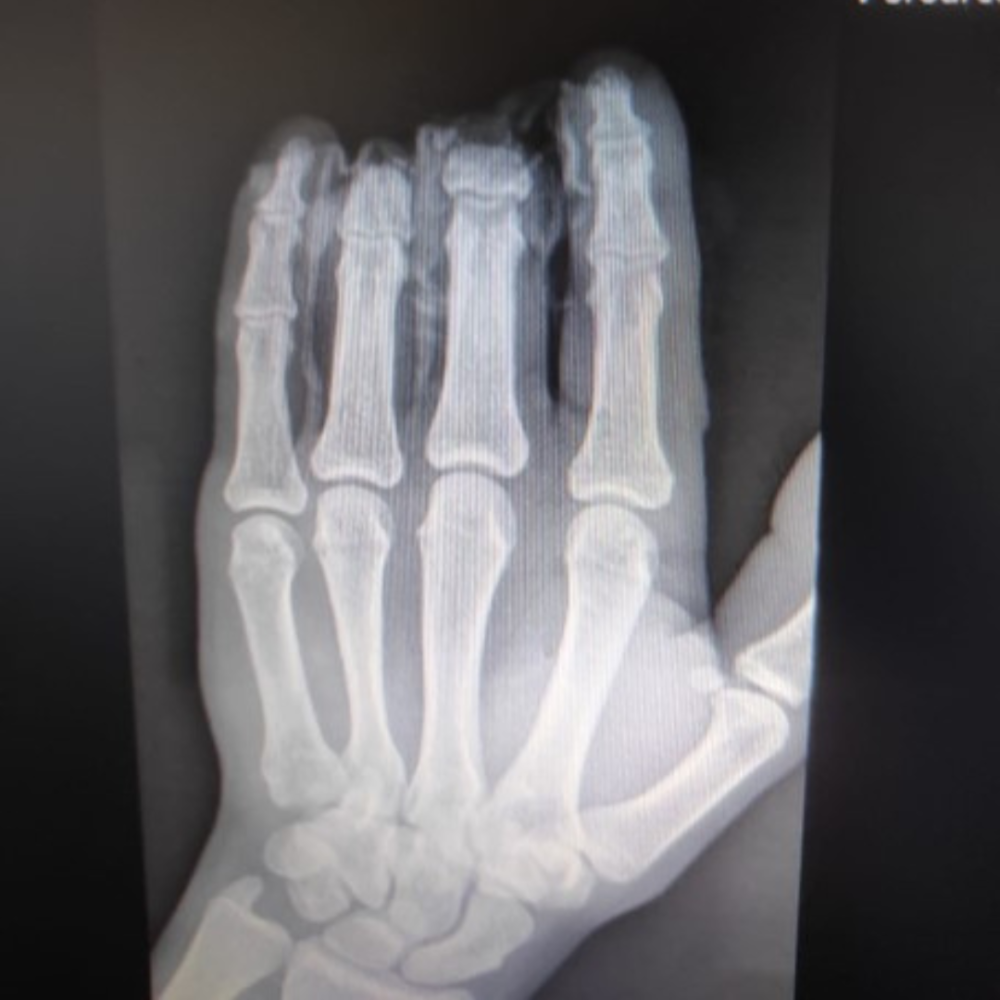

9 marca 2024 roku w 5 Wojskowym Szpitalu Klinicznym, wykonano zabieg replantacji dwóch palców u 22-letniego pacjenta z Łomży. Dla Zespołu szpitala to już niemal rutyna, ponieważ od dwóch lat 4 razy w miesiącu pełni dyżury w nieformalnym „serwisie replantacyjnym”.

Lekarze operujący i lekarz anestezjolog przyjechali z domu, rezygnując ze swojego wolnego czasu, po to aby pomóc 22-latkowi. Uraz palców był wyjątkowo ciężki, ponieważ doszło do zmiażdżenia brzegów rany i rozległego uszkodzenia naczyń, a organizowanie zespołu zawsze trwa i zabiera ceny czas. Operacja  rozpoczęła się o północy i trwała około 8 godzin. Wymagała przeszczepów żył i skomplikowanych procedur jak płaty żylno-żylne, które wyjątkowo rzadko są potrzebne w takich sytuacjach.